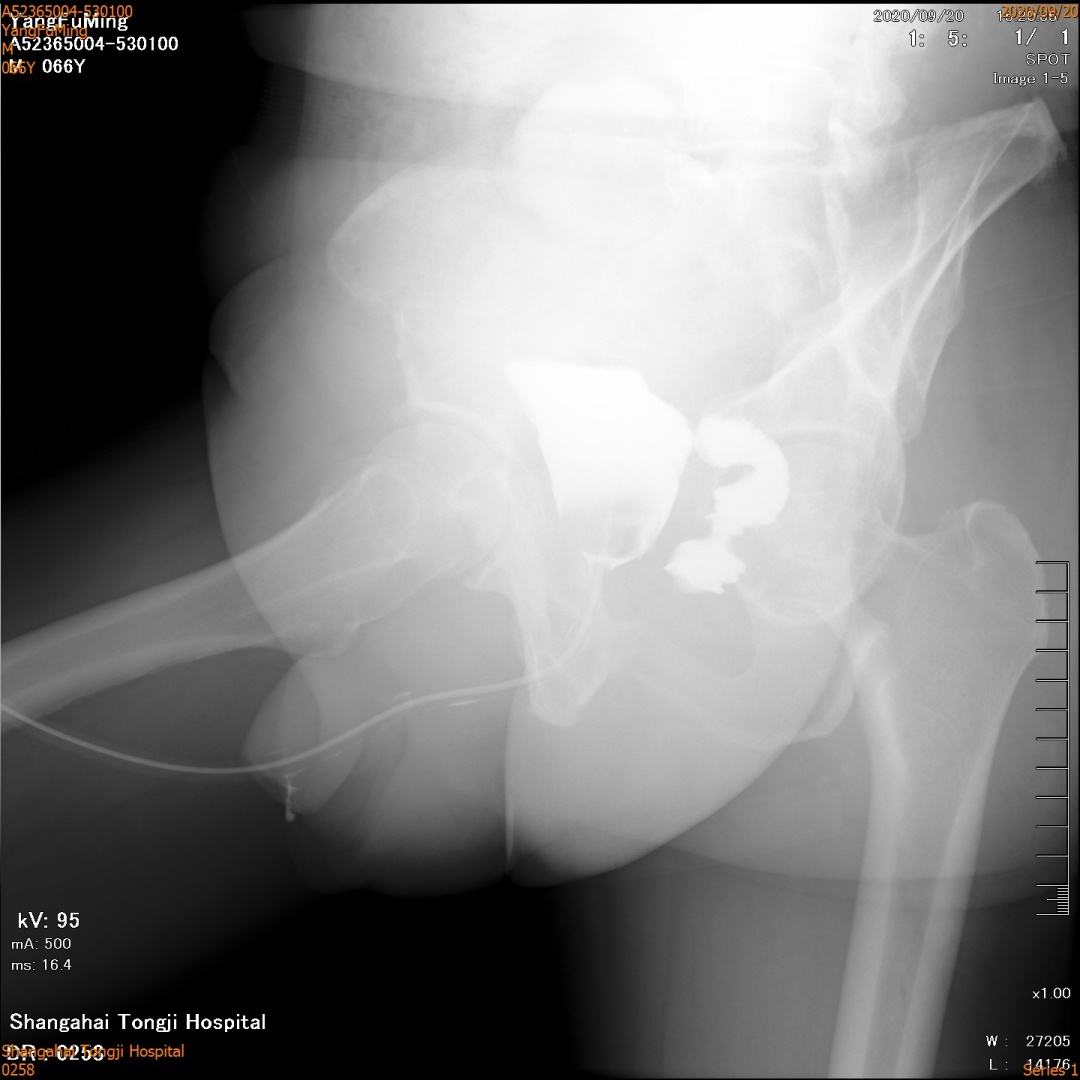

在现代医学技术的发展下,前列腺癌的治疗已经越来越成熟。然而,即使在根治手术后,患者仍可能面临着一些并发症,其中最常见的就是膀胱直肠瘘。这种疾病严重影响患者的生活质量,让他们不得不忍受痛苦和尴尬。 经肛门路径(膀胱)尿道直肠瘘修补术的出现,帮助前列腺癌术后膀胱直肠瘘患者重获了健康和自信。这种前列腺癌根治术后直肠瘘修补术,不仅可以有效治疗直肠瘘,还可以提高患者的生活质量。 王先生今年66岁,2年前因前列腺增生进行了经尿道前列腺电切术,术后病理提示前列腺癌。半年后,王先生进行了腹腔镜下前列腺癌根治性切除术。然而,术后3个月,王先生发现自己肛门内总有尿液流出,随后在外院进行了膀胱造瘘及结肠造瘘的治疗。治疗后没有排尿困难,但是尿失禁和性功能障碍一直困扰着他,严重影响其生活,总体满意度未达其预期。 之后,王先生经人介绍来到了同济大学附属同济医院就诊。经同济大学附属同济医院泌尿外科罗华荣主治医师诊断后,决定予以经肛门膀胱直肠瘘修补术。术中用电切镜沿瘘口切开一圈,将膀胱粘膜与直肠粘膜分开。术后6周左右拔出导尿管,王先生可以自行排尿,没有再次发生肛门内漏尿的情况。 ▲术前膀胱造影检查

▲膀胱镜检查瘘口